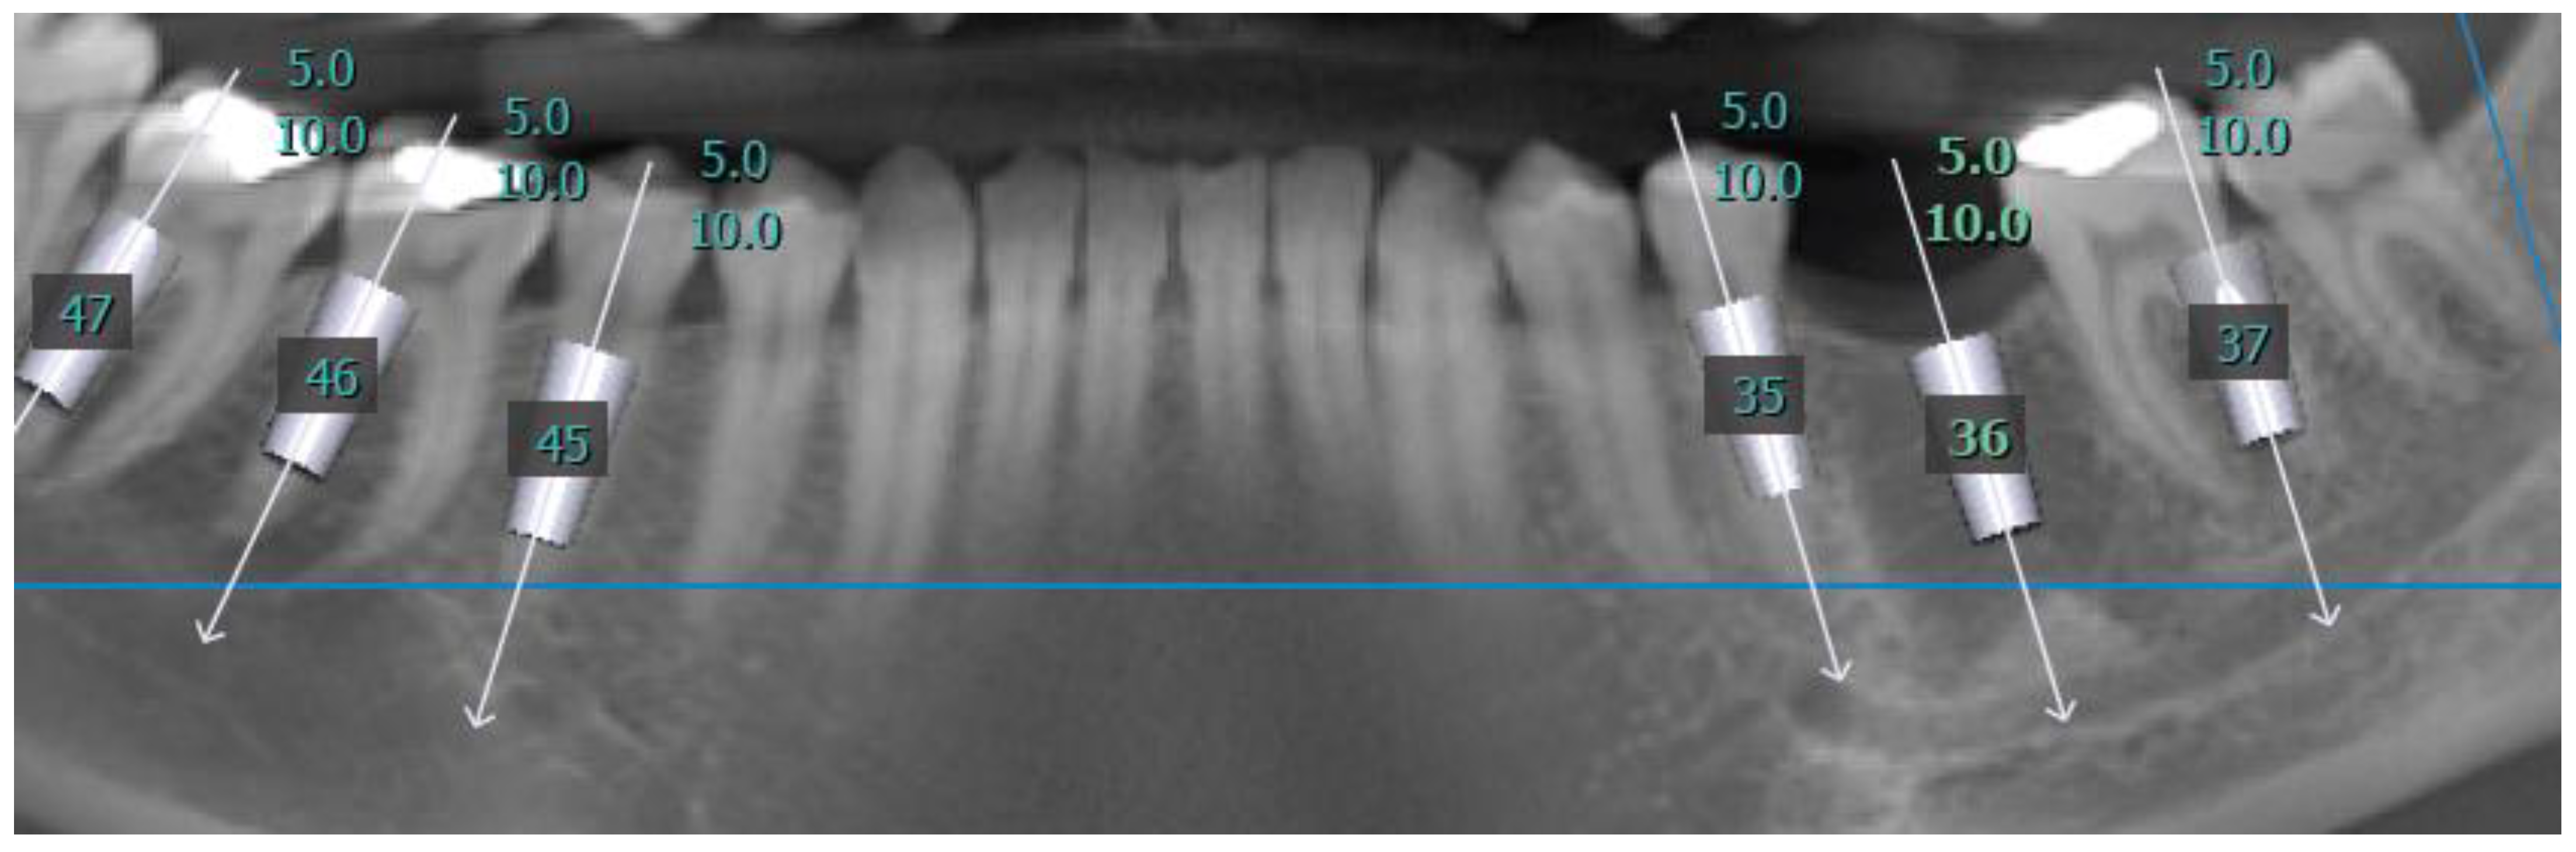

2.2. Procedure

2.3. Measurements

3. Results

3.2. Distance Measurements